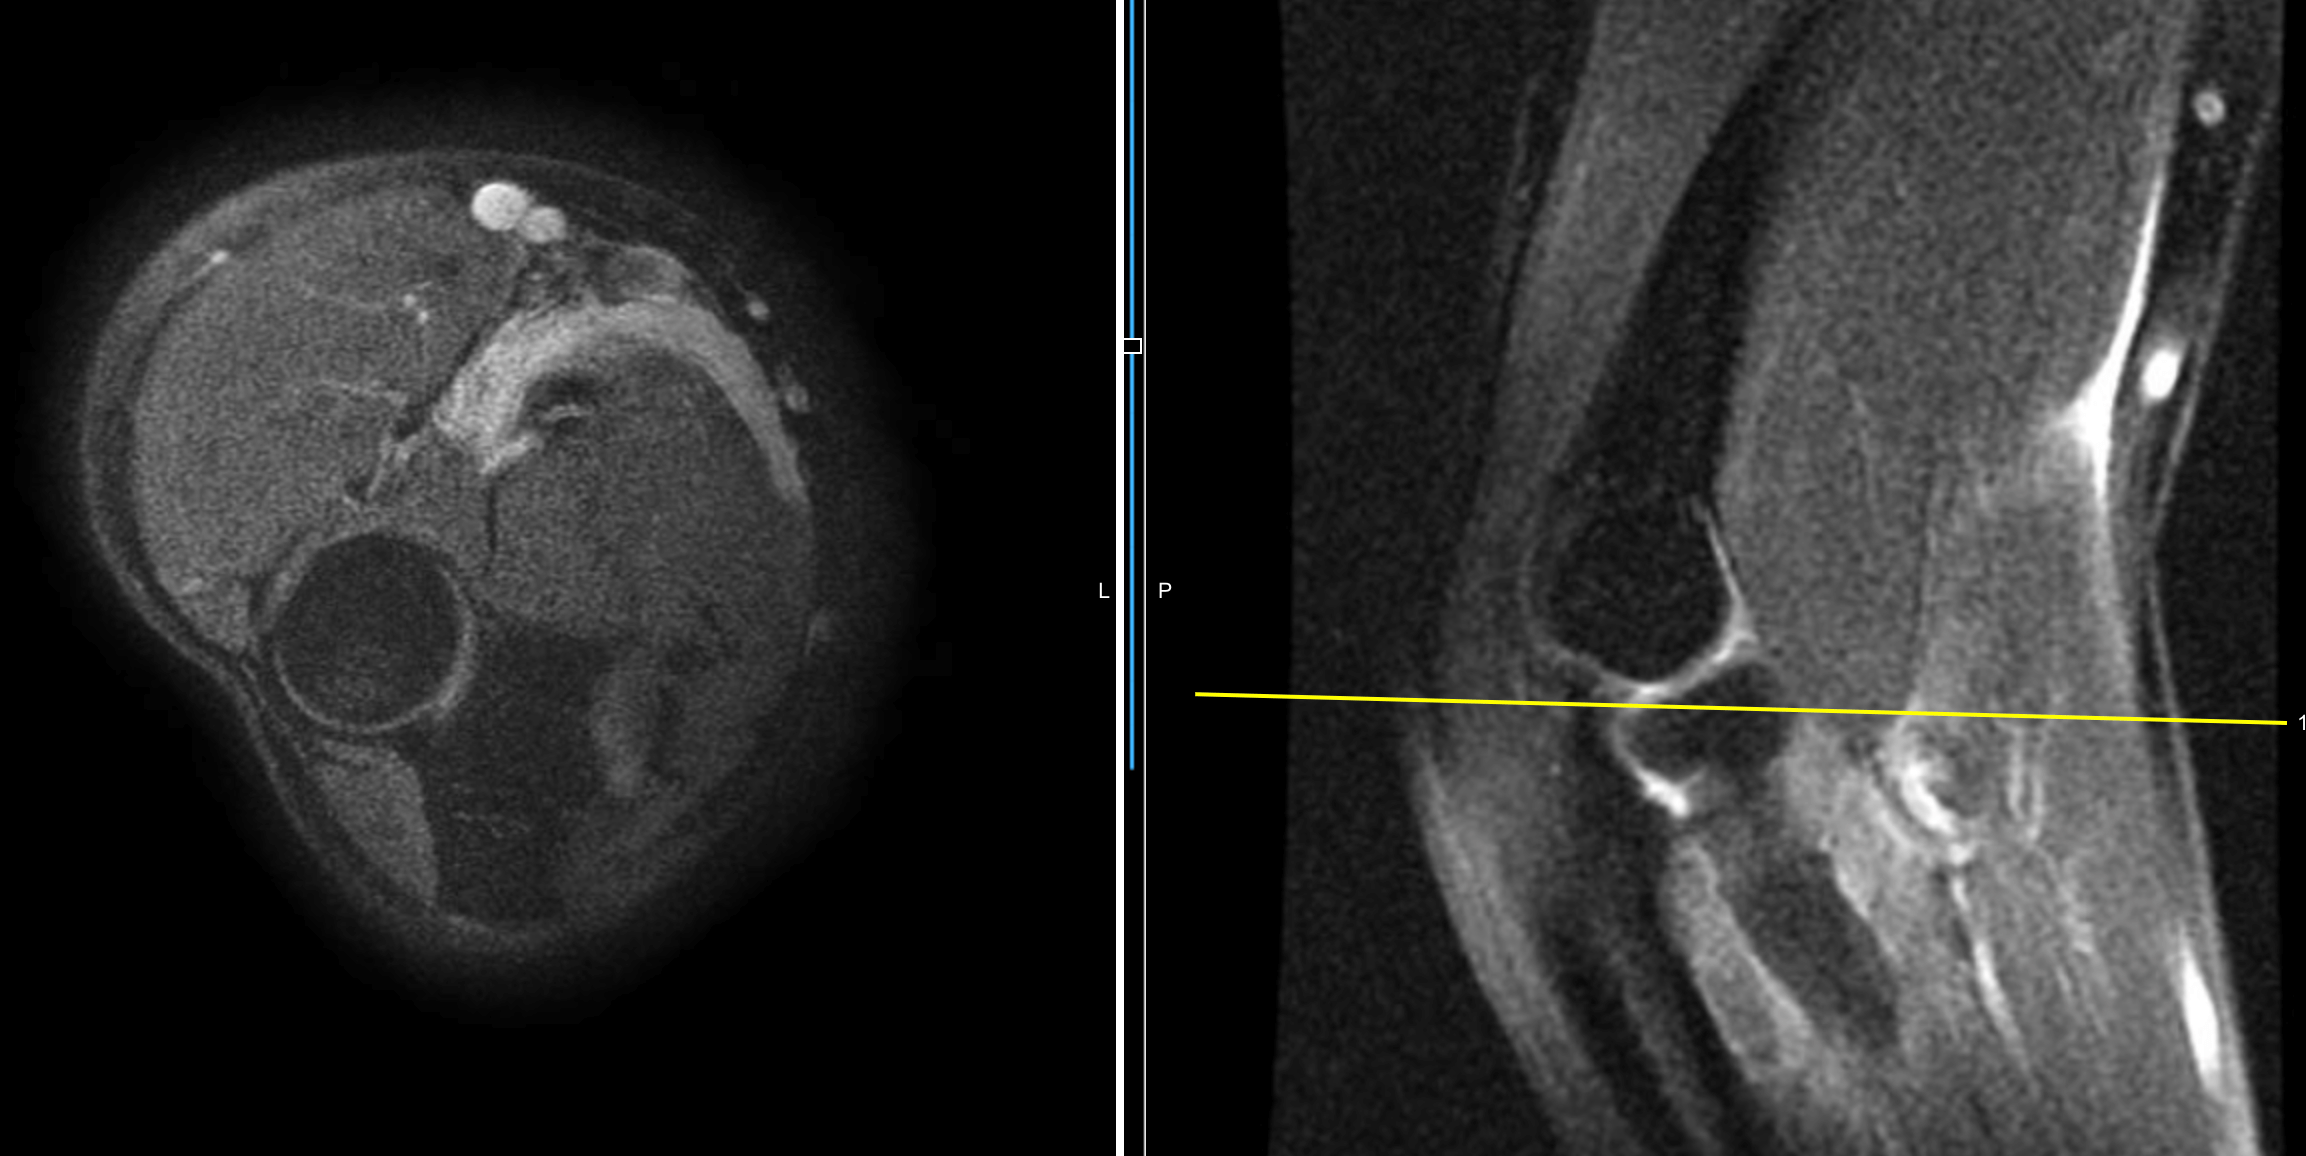

Bíceps distal roto: En esta imágen podemos observar como el tendón largo del bíceps braquial se retrae por sufrir un arrancamiento de su inserción en la tuberosidad del radio a nivel del codo.

Lesiones de ligamentos colaterales del codo: Los ligamentos colaterales del codo son el interno (UCL o ligamento colateral cubital) y el externo (RCL o ligamento colateral radial) y estos ayudan a la estabilidad en el plano coronal; es decir evitan el movimiento lateral de la unión del cúbito - radio y húmero distal. Pueden sufrir lesiones si existen fuerzas que sobrepasan su resistencia, las fuerzas en varo o valgo. En estos casos es posible realizar ecografía o ultrasonido para detectar su lesión, o hasta una resonancia magnética.